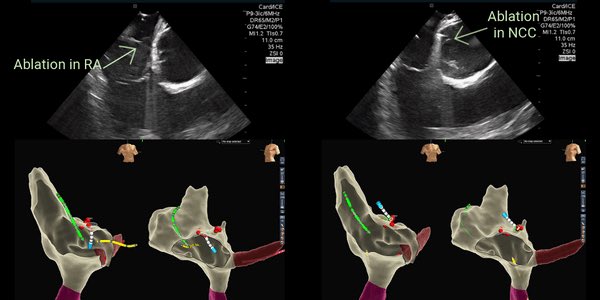

AT ablation from RA/NCC. intracardiac echo is essential #viewflex@Frances_Salmon2